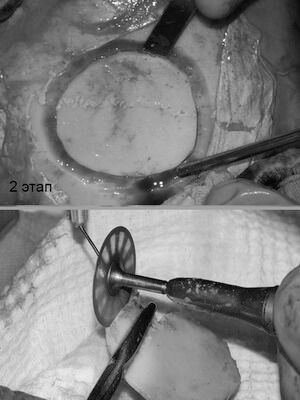

У пациентки выявлена редкая разновидность остеомы - губчатая форма с обширным распространением на лобную кость. Принято решение о косметическом бикоронарном и остеопластическом доступе на лобной кости и лобной пазухе. Разрез спрятан в волосах. Опухоль удалена до твердой мозговой оболочки с , и с местом прорастания в лобную пазуху. Дефект закрыт расщепленным костным аутотрансплантатом с теменной области. Послеоперационное фото сделано на 7 сутки. Отсутствие отеков, гематом, быстрая реабилитация- особенность данной методики.